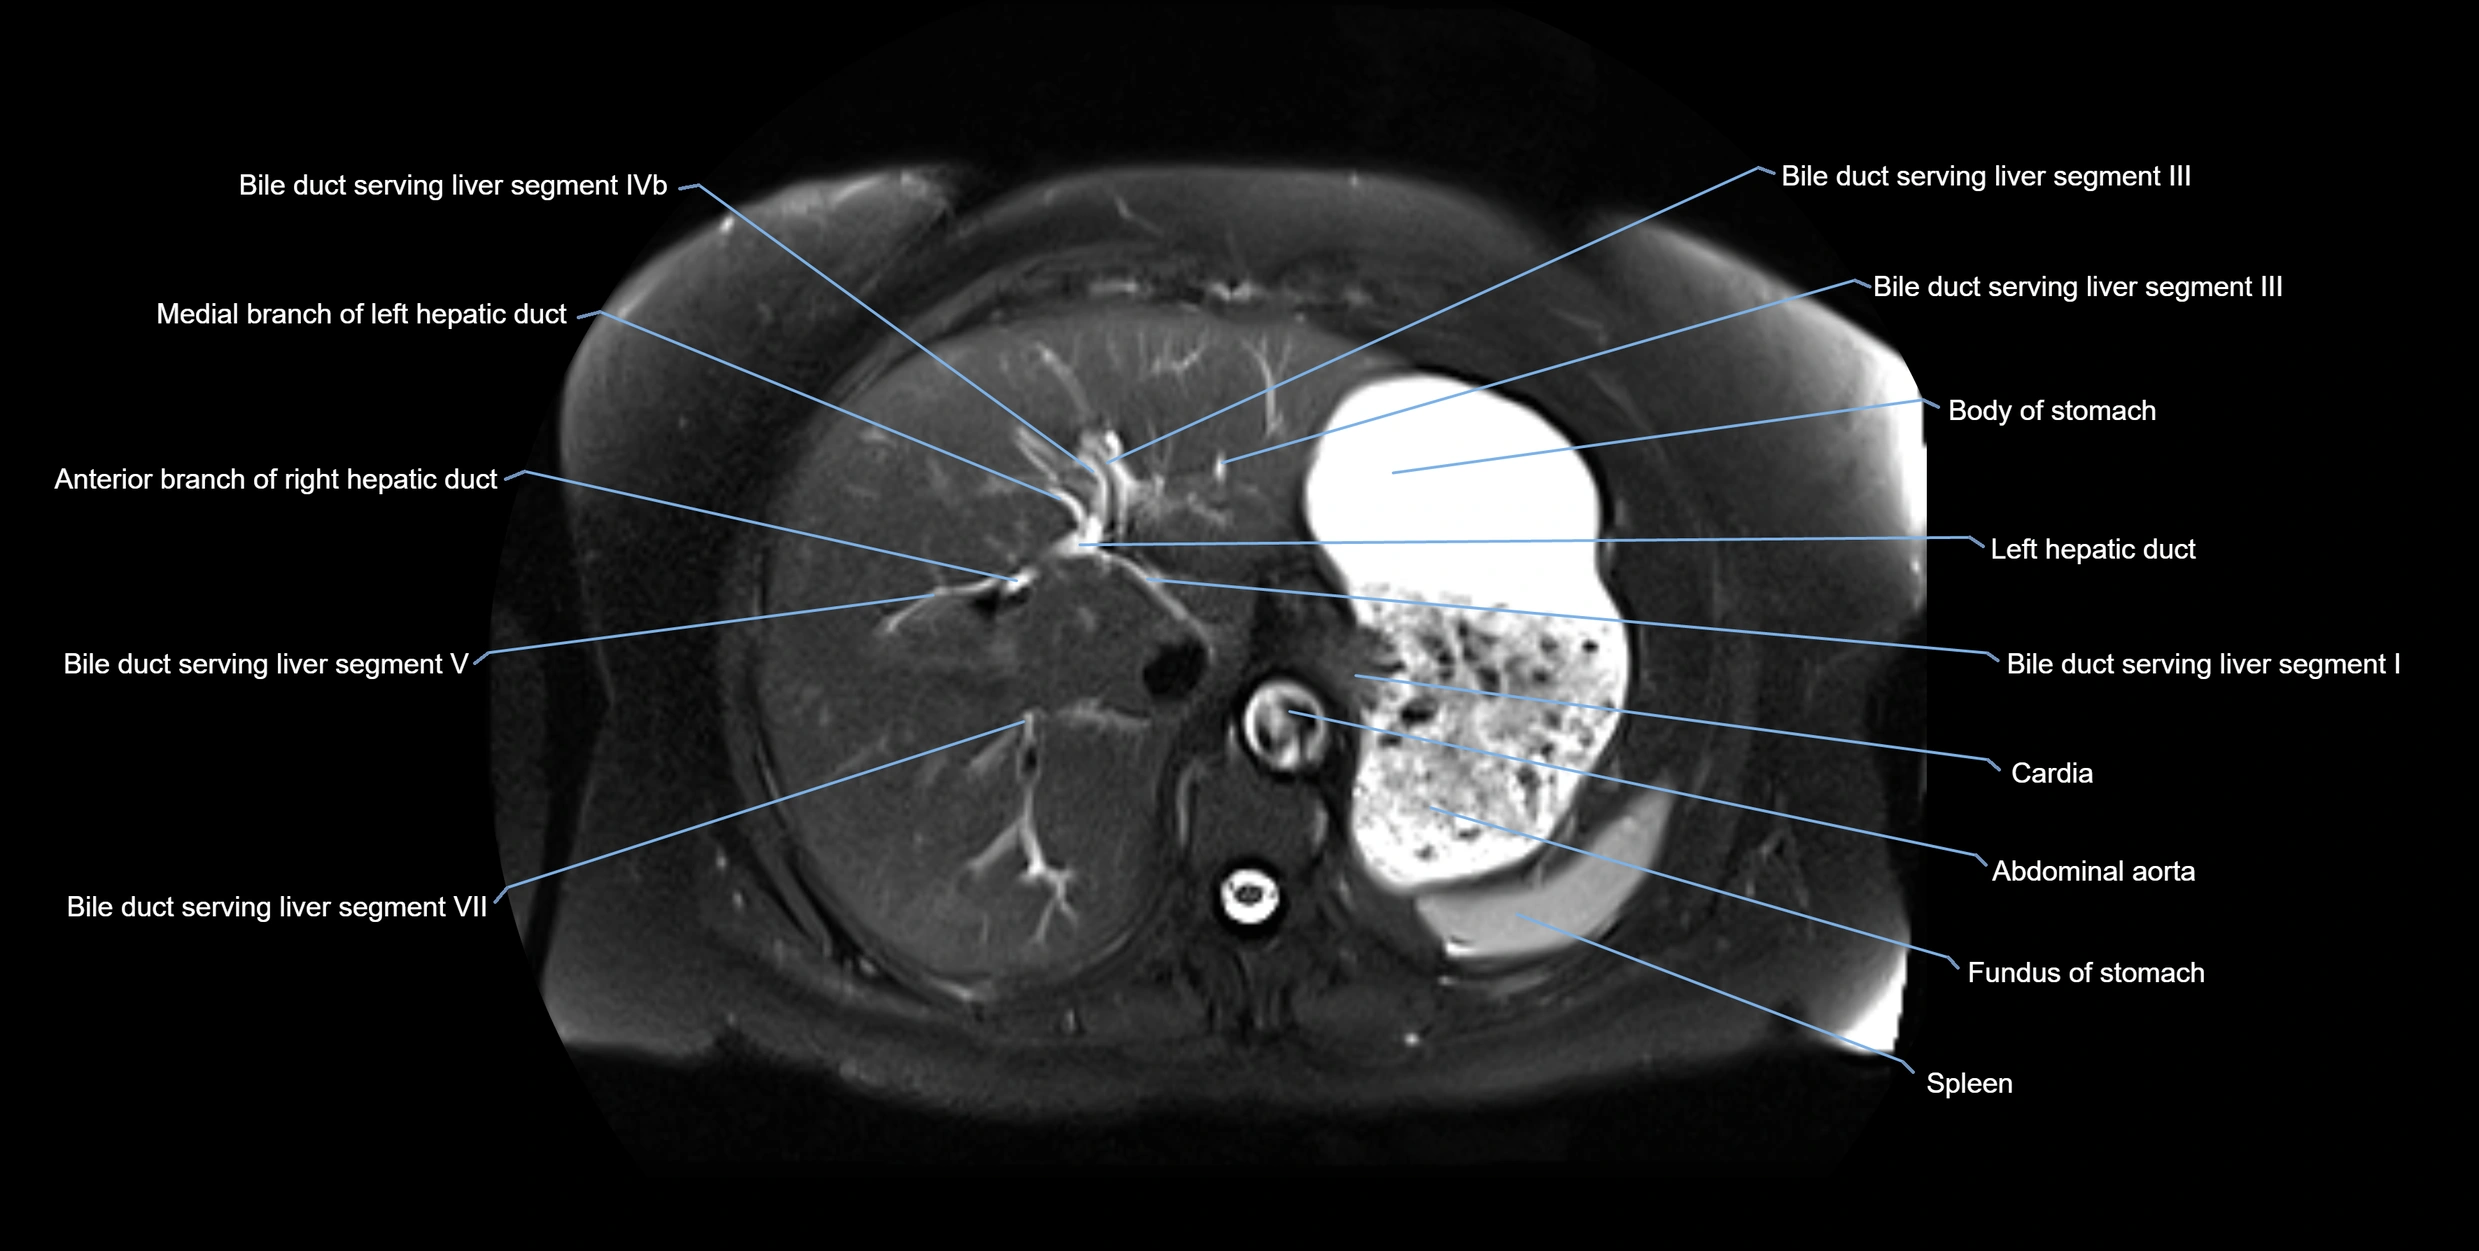

MRI Appearance

T1-weighted images:

• Not typically visualized unless dilated; appears as low signal tubular structure if seen

• Surrounding pancreatic parenchyma shows intermediate signal

T2-weighted images:

• Duct fluid appears bright

• Accessory duct seen as a fine high-signal tubular structure in pancreatic head

STIR (Short Tau Inversion Recovery):

• Duct fluid remains bright

• Surrounding fat suppressed, improving duct conspicuity

T1 Fat-Sat Post-Contrast:

• Normal duct does not enhance

• Surrounding inflammatory or neoplastic changes may enhance

T2 Fat-Saturated HASTE (single-shot):

• Accessory duct: bright, thin linear structure in pancreatic head

• Stones, strictures, or air bubbles appear as dark filling defects

• Excellent for rapid evaluation of duct patency

T2 TSE Fat-Saturated 3D (MRCP sequence):

• Duct visualized as a continuous bright tubular structure joining or parallel to the main pancreatic duct

• Allows 3D reconstruction of ductal anatomy and variants

• Excellent for diagnosis of pancreas divisum

Thick-slab T2 Fat-Saturated HASTE:

• Shows the accessory duct as part of the biliary–pancreatic system in a projectional image

• Highlights communication with main pancreatic duct and opening into the minor papilla

• Filling defects (stones, strictures) seen as dark spots within bright fluid

MRI image

image